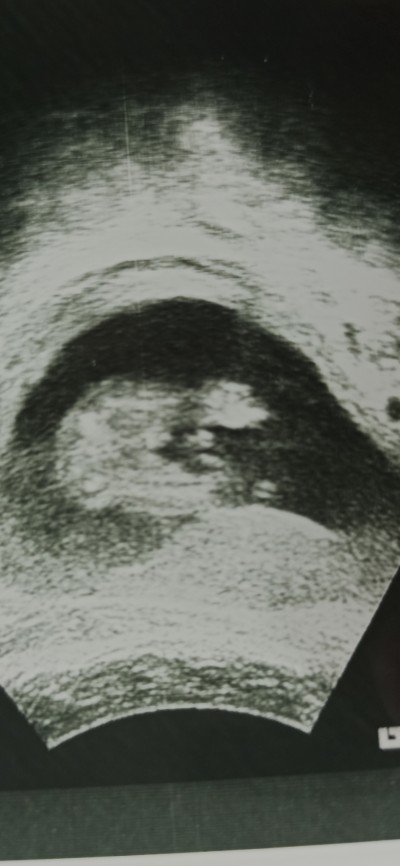

Sizce pipimi yoksa kordonmu bu 16 haftalik ultrason görüntüsü doktorum erkek dedi ama emin olamadı tam göstermedi bebis :)

Kız kaç tane post paylaşmışsın  ama erkeğe benziyor